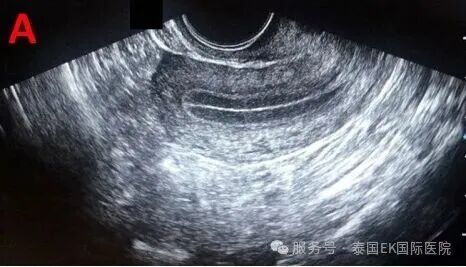

三线征:你的内膜准备好了吗?